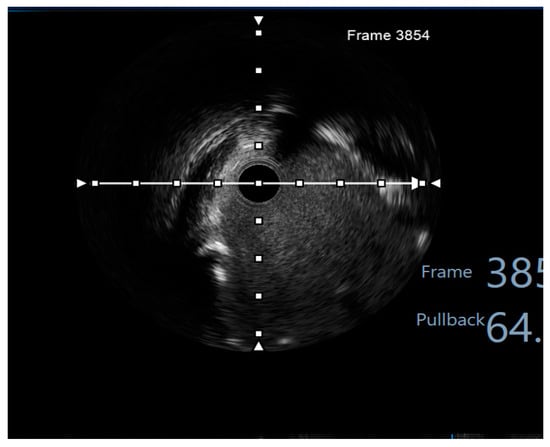

2. Case Presentation